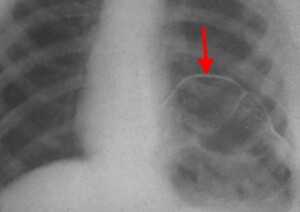

- Лучевая диагностика. Выполняется рентгенография и КТ грудной полости, КТ брюшной полости. Выявить разрыв на рентгенограмме можно только при пролапсе органов пищеварения в область грудной клетки. Для уточнения локализации травматического дефекта грудобрюшной перегородки, дифференциальной диагностики травмы и релаксации органа осуществляется контрастная рентгенография желудка либо ирригография. Просматривается желудок или петли кишечника в левой половине грудной клетки, определяется смещение пищевода.

КТ органов грудной клетки/брюшной полости. Травматический дефект в передних отделах диафрагмы справа с эвентрацией кишечника, сальника, кровеносных сосудов в грудную полость

Рентген. Рентгенологическое исследование является решающим в диагностике релаксации, при этом определяются следующие симптомы:

- стойкое повышение уровня расположения соответствующего купола диафрагмы до 2 - 5 ребра;

- в горизонтальном положении диафрагма и прилежащие к ней органы брюшной полости смещаются кверху;

- контур диафрагмы представляет собой ровную, непрерывную дугообразную линию.

Нередко выявляется ателектаз нижних отделов легкого и смещение средостения.

Релаксация диафрагмы рентген (левый купол)